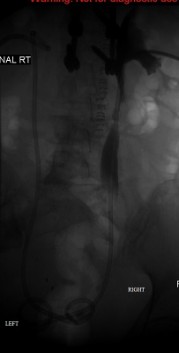

Right and left ureters after nephroureteral stenting

Published July 12, 2014 at 179 × 353 in Bilateral insertion of nephroureteral stents after balloon dilation of malignant obstruction of the distal ureters. Ken U. Ekechukwu, MD, MPH, FACP..

Right and left ureters after nephroureteral stenting.